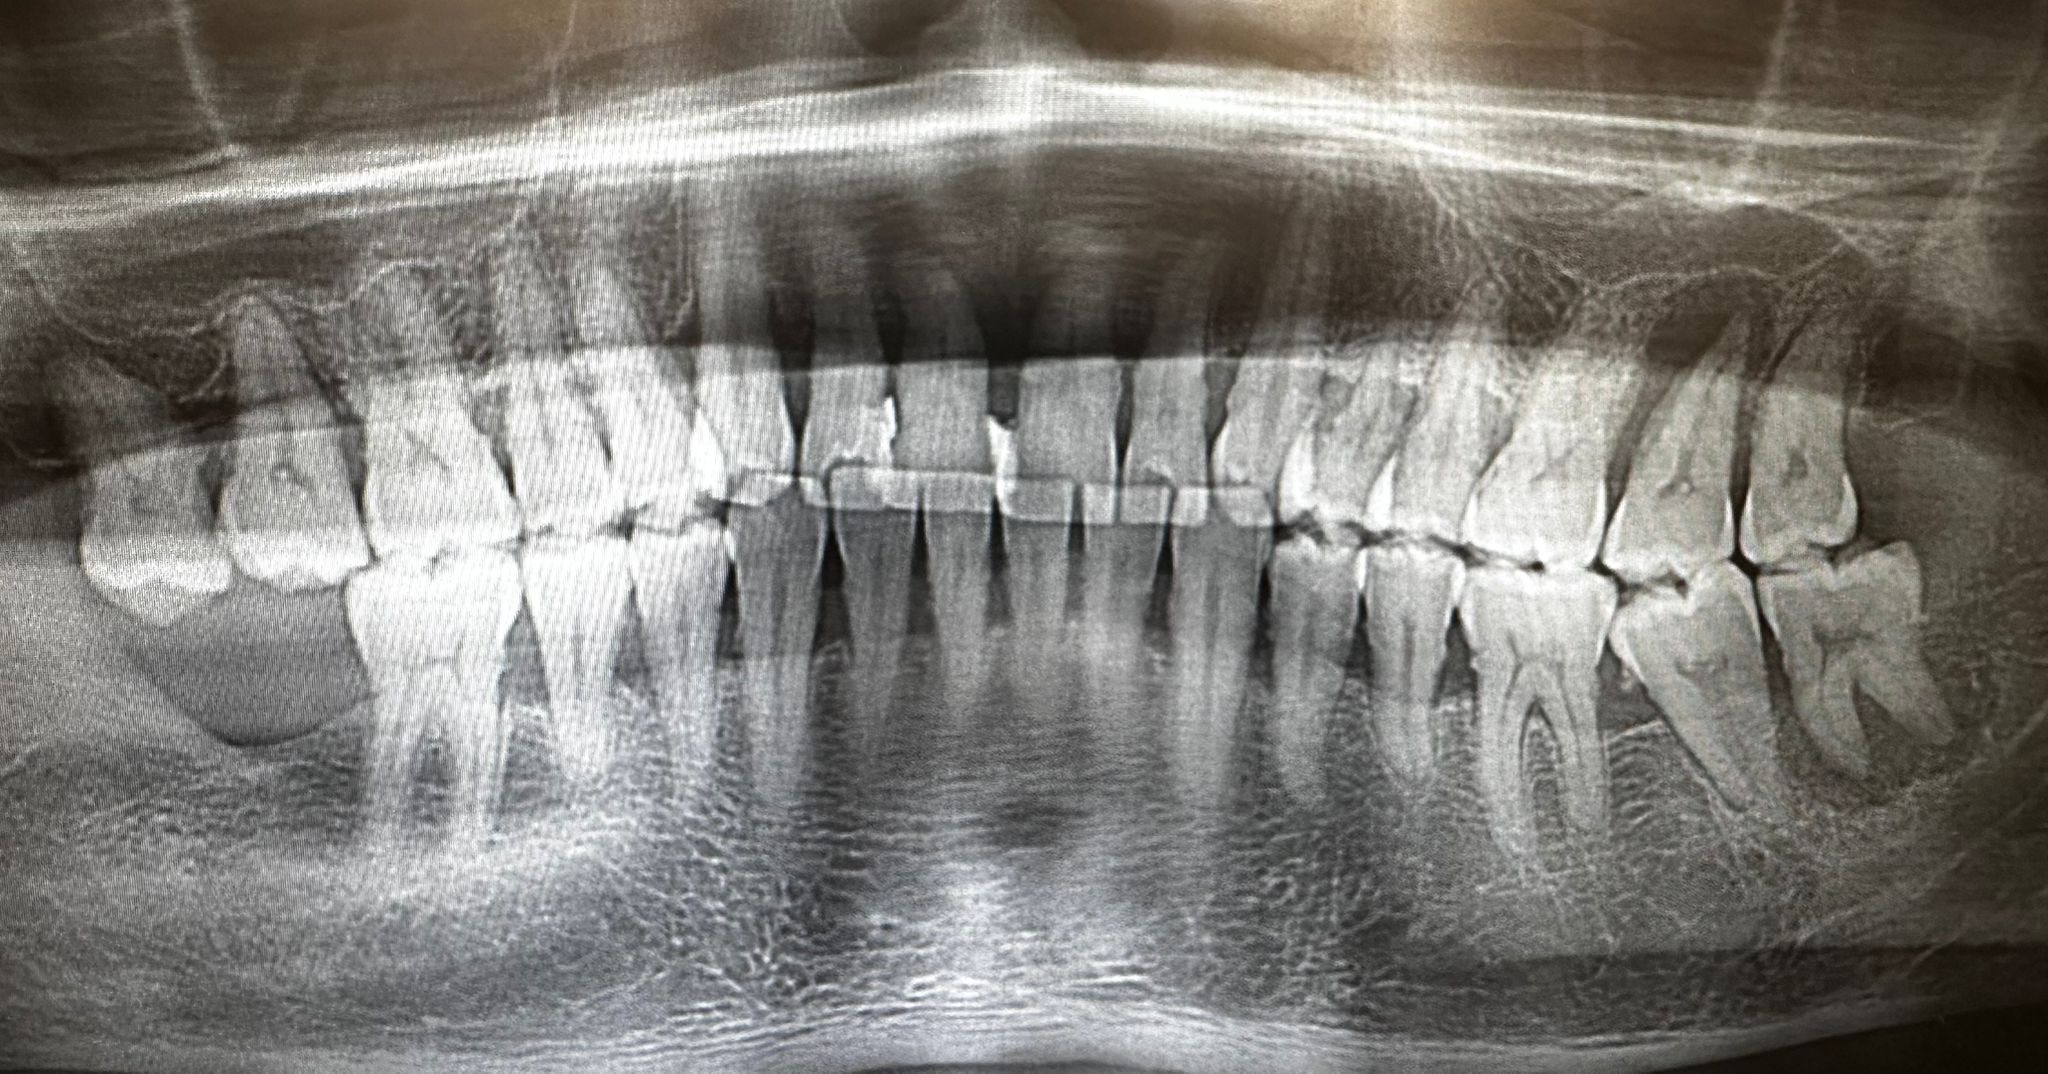

Este paciente acudió a mi consulta referido por otros pacientes, con un estado periodontal comprometido, una sobrecarga funcional muy marcada y una movilidad severa de los incisivos superiores. Era un paciente con gran fuerza masticatoria, un volumen óseo importante, pero con una calidad ósea deficiente.

En la implantología convencional, esto suele implicar múltiples extracciones, tiempos de cicatrización, prótesis removibles provisionales, injertos óseos y, finalmente, una rehabilitación fija más voluminosa, porque el espacio protésico ya no es el de unos dientes naturales.